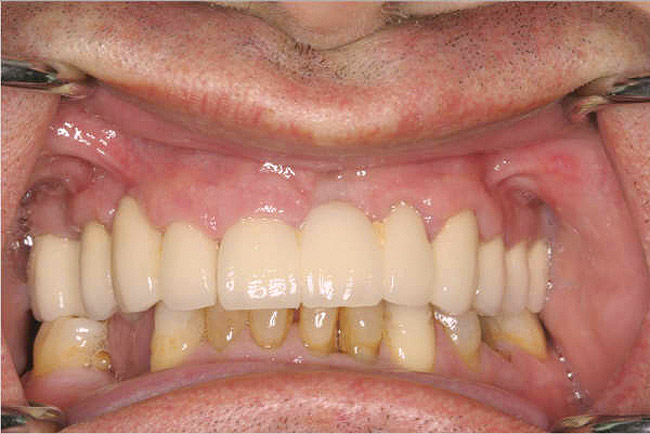

Fixed Restorations: Large Segment/Full Arch

For large-segment/full-arch fixed prostheses, the critical distance is 15 mm. If the distance from the implant platform to the occlusal table is less than 15 mm, then the prosthetic material indicated is porcelain-fused-to-metal (PFM) (Figure 3). If the distance is greater than 15 mm, then a hybrid prosthesis should be used (Figure 4).

The 15-mm measurement is important because of the physical properties of the restorative materials. Acrylic requires bulk for strength. If there is less than 15 mm of distance from the implant platform to the occlusal table, there will not be sufficient space to achieve the bulk of acrylic necessary to provide strength for the prosthesis. The unfortunate result will be continual repair of fractures for the life of the prosthesis.

Likewise, PFM restorations have difficulties when too much space is available. At dimensions greater than 15 mm from the implant platform to the occlusal table, the control of surface porosity across the metal substructure becomes difficult because of variations in cooling and heating rates across the metal,10 which in turn makes it difficult to bake porcelain to the metal substructure. The result is the high possibility of future unwanted complications of porcelain fracture.11

There is also a considerable difference in the laboratory costs for these types of prostheses. A PFM restoration requires more metal to achieve a uniform 2-mm thickness and is more technique-sensitive (Figure 5 and Figure 6). A hybrid prosthesis requires less metal and uses acrylic and denture teeth for the remaining restoration (Figure 7 and Figure 8). Understanding the impact that the 15-mm height has on which type of restoration is required gives the dentist the ability to quote a more accurate fee to the patient.

Figure 3   A crown height space < 15 mm necessitates a PFM material selection.

Figure 3

Figure 4  A crown height space > 15 mm necessitates a hybrid restoration.

Figure 4

Figure 7   A hybrid restoration requires less metal to fabricate.

Figure 7

Figure 8   A hybrid restoration requires less metal to fabricate.

Figure 8